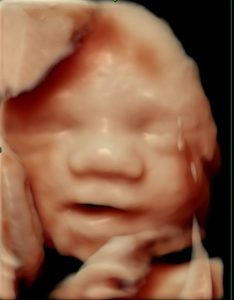

Uge 29: Fosterets udvikling

Fosteret er omkring 38–40 cm langt og vejer cirka 1.300–1.400 gram.